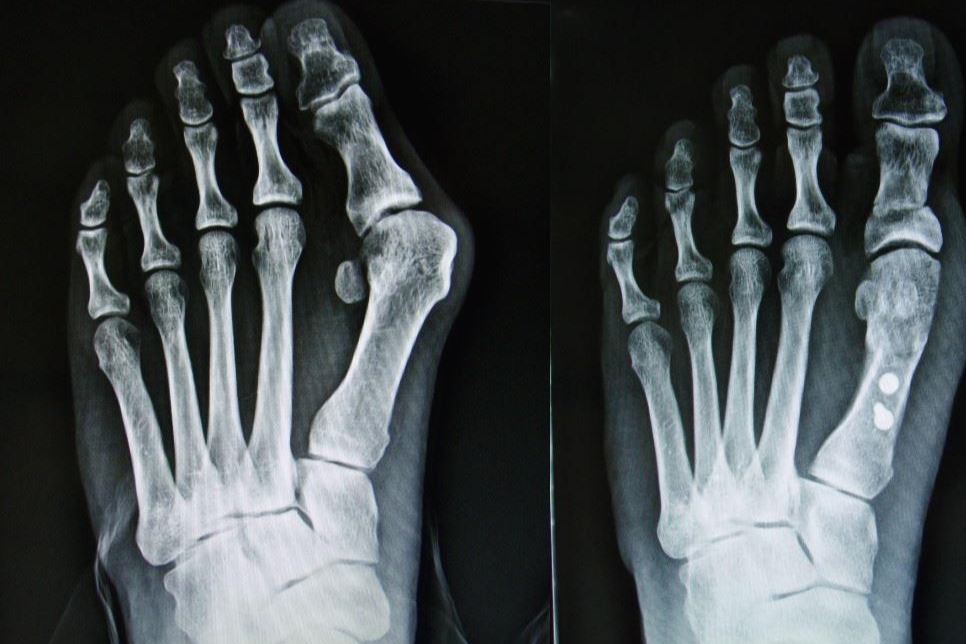

"구두를 신으면 발이 아프다" 라고 하는 고민의 대부분은 무지 외반증에 기인하고 있습니다.

무지 외반증은 문자 그대로 발 외반증(엄지)가 다른쪽 발가락쪽으로 휘는 것을 말합니다.